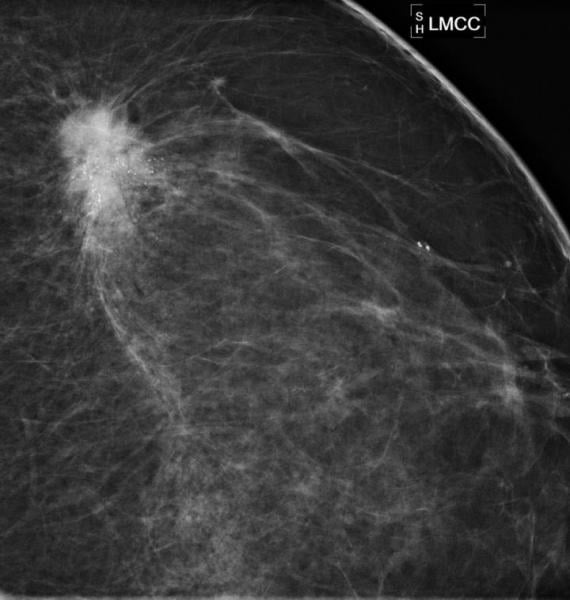

December 9, 2014 — A study of breast cancers detected with screening mammography found that strong family history and dense breast tissue were commonly absent in women between the ages of 40 and 49 diagnosed with breast cancer. Results of the study were presented at the annual meeting of the Radiological Society of North America (RSNA).

"Screening recommendations for this age group continue to be debated," said Bonnie N. Joe, M.D., Ph.D., associate professor in residence and chief of women's imaging at University of California, San Francisco (UCSF). "Recent publications have suggested risk-based screening based on family history and breast density. However, our study shows that this approach would miss a significant percentage of invasive cancers and could potentially be dangerous."

"Notably, we found that almost 90 percent of the invasive cancers we would have missed using risk-based triage had positive receptor status, meaning they were very treatable and worth finding early," Joe said.

Of the 136 breast cancer cases identified, 50 percent were diagnosed as invasive, and 50 percent were diagnosed as ductal carcinoma in situ (DCIS), an early noninvasive form of breast cancer, although 88 percent of DCIS cases were intermediate or high grade.

A very strong family history was absent in 90 percent of patients, and extremely dense breast tissue was absent in 86 percent. Seventy-eight percent of patients had neither strong family history nor extremely dense breasts, including 79 percent of the cases of invasive disease.

"Our results show that by exclusively using a risk-based approach to screening mammography, we could potentially miss more than 75 percent of breast cancers in women in their 40s, thereby eliminating most of the survival benefit from screening mammography that has been previously shown in randomized controlled trials," Joe said.

"Based on our current knowledge and evidence shown in previous trials, it is still safest to get annual mammograms starting at age 40 in order to maximize the survival benefit of screening mammography," Joe said.